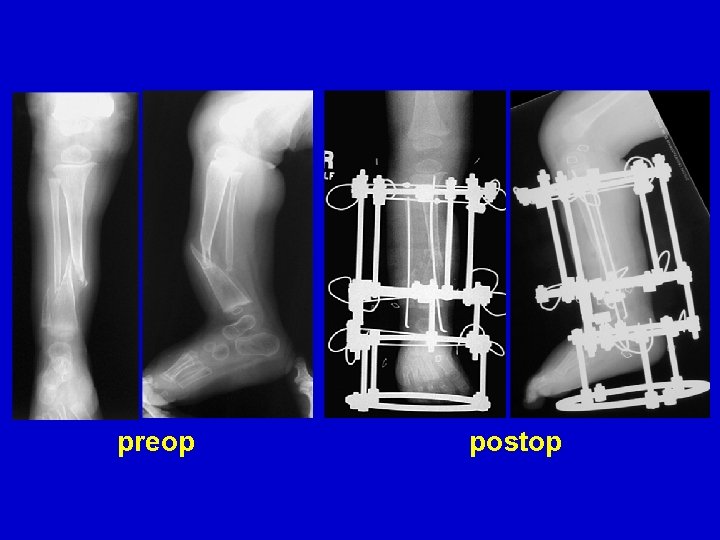

Treatment Type III • Closed distraction + compression • Gradual deformity correction • ± Lengthening • ± IM Rod (late)

distraction of CPT follow-up

pre-op compression healed

Treatment Type III • Closed distraction • Gradual deformity correction • ± Lengthening • ± IM Rod (late)

distraction of CPT follow-up